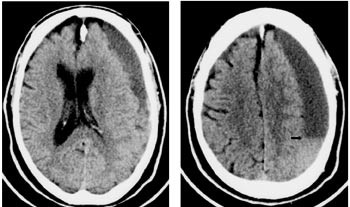

Standard blodprøver var normale, men cerebral CT viste en ca. 2 cm bred homogen subdural effusjon som strakte seg over størstedelen av venstre hemisfære. Det var kompresjon av sideventriklene og overskyting av midtlinjestrukturene mot høyre (fig 1).

Når det anbefales å foreta en cerebral CT-undersøkelse av alle pasienter med mistenkt hjerneslag (1), er det først og fremst av differensialdiagnostiske grunner, noe vår pasient viser betydningen av. Et normalt funn på cerebral CT kan derimot ikke benyttes til å avkrefte diagnosen hjerneslag dersom de kliniske symptomene er typiske. Symptomene hos vår pasient ble oppfattet som forholdsvis beskjedne, noe som står i kontrast til hematomets størrelse radiologisk bedømt. Dette kan illustrere at rommelige intrakraniale plassforhold hos eldre gjør at ekspansive prosesser i mange tilfeller må nå en betydelig størrelse innen de gir symptomer. Men det kan også skyldes at pasientens premorbide fysiske funksjonsnivå, og dermed det aktuelle funksjonstapet, ble underestimert. Vi fikk etter hvert vite at han hadde vært en ivrig danser helt frem til det aktuelle, noe som stod i åpenbar motsetning til funksjonsnivået ved innleggelsen.